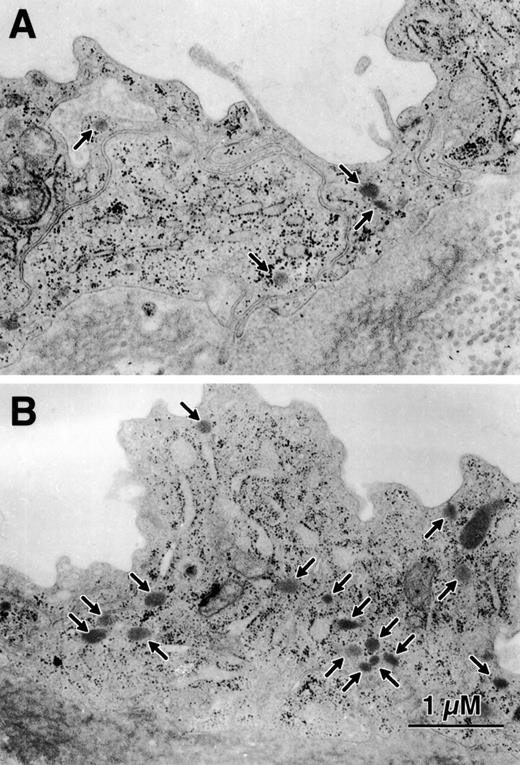

HUVECs were collected from 6 preterm infants ranging from 23 to 26 weeks of gestation and from 6 term infants greater than 38 weeks of gestation. Ultrastructural observation was performed by an observer blinded to the gestational age of the infants from whom the endothelial cells were collected and showed that intact endothelial cells lined all of the umbilical cords. Weibel-Palade bodies were morphologically identified35 36 as small, membrane-bound, rod-shaped organelles of moderate density that were located in the cytoplasm of the umbilical cord endothelial cells. There were few Weibel-Palade bodies in endothelial cells of very premature infants and the number increased with increasing gestational age (Figs 5 and 6).

The number of Weibel-Palade bodies per HUVEC is less in endothelial cells from preterm infants. This figure is representative of the data in Fig 5. (A) is from a 23-week gestation infant and (B) is from a term infant. Here there are 4 to 5 times as many Weibel-Palade bodies (arrows) in the cytoplasm of the term infant compared with the preterm infant.

Preterm umbilical vein endothelial cells have fewer Weibel-Palade bodies than term cells. HUVECs were viewed by transmission electron microscopy for quantitative morphology. The mean numerical density (NV) represents the number of Weibel-Palade bodies per cubic micrometer of nonnuclear cytoplasm. The difference between term and preterm endothelial cells is significant (P = .01).